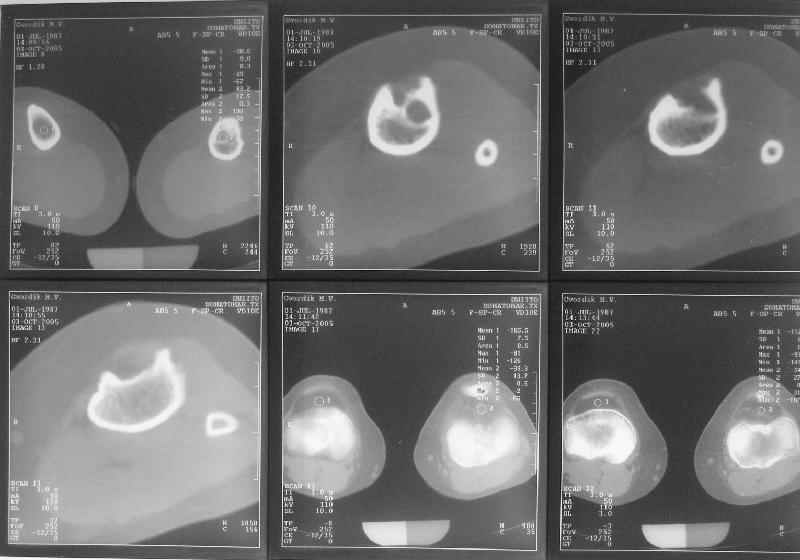

Продолжение обсуждения, начатого в октябре прошлого года (см. здесь) Наконец-то оперировали эту пациентку. Биопсию сделали - опухолевого ничего нет. Пока все участвовавшие в обследовании смежные специалисты и ортопеды сошлись, что это молокальная монооссальная фиброзная дисплазия. 20 марта наложили аппарат, сделали чрескожную остеотомию. К 3 апреля все докрутили. Сегодня заштифтовали. Начальные и итоговые снимки в приложении. Рекурвацию можно было еще немного больше устранить, и чуть кзади сместить диафиз. Но вроде и так ничего выглядит, по сравнению с тем, что было. Комментарии приветствуются.

ничего не понимаю в детской и ортопедии, но в боковой проекции нет рекурвации,

а даже немного гиперкоррекция, что по-моему есть хорошо. Кортикалы по задней стенке совпадают, диафиз на одну неправду кзади.

Есть клиновидный диастаз, контакт основных отломков на очень небольшой площади только в задненаружном отделе. Так что там скорее межотломковая дистракция, а не компрессия.